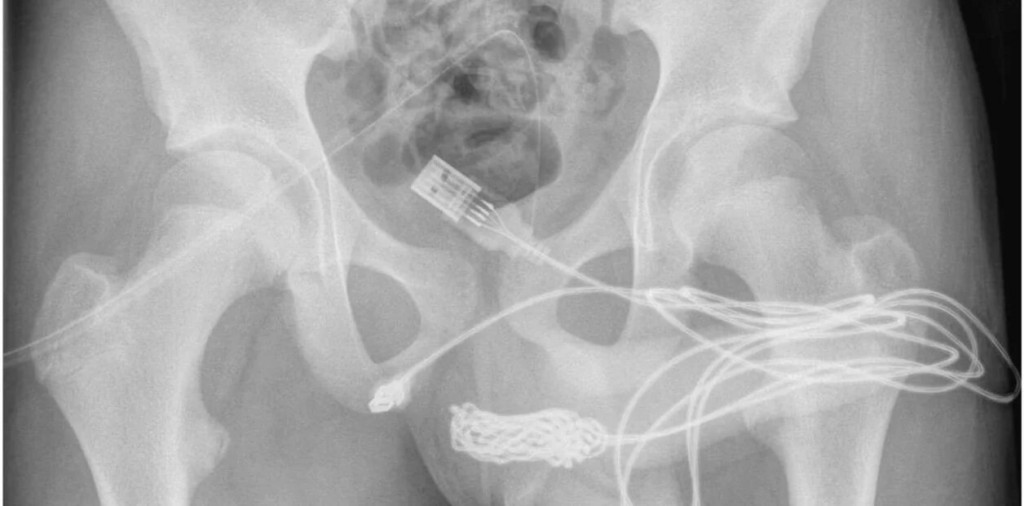

Un joven de 15 años que orinaba sangre y tenía fuerte dolores en la zona genital terminó convertido en el paciente más extraño de los últimos años. Los médicos encontraron que tenía un larguísimo cable USB enredado dentro de su pene.

"Se descubrió que los dos puertos distales del cable USB sobresalían del meato uretral externo, mientras que la parte media del cable anudado permanecía dentro de la uretra. El paciente era un adolescente sano y en buena forma física sin antecedentes de trastornos de salud mental”, indicaron los médicos en un informe de ScienceDirect.com.

Los médicos intentaron retirar el cable con una pinza, pero no tuvieron más remedio que practicar una cirugía, muy complicada por los efectos adversos que puede generar una intervención en la zona.

"Se realizó una incisión penoescrotal longitudinal sobre el cuerpo extraño palpable y se realizó una disección cuidadosa a través de los tejidos más profundos, dividiendo el músculo bulboesponjoso", detallaron los expertos al explicar el procedimiento.

Y agregaron: "Ambos extremos del cable se sacaron con éxito a través del meato uretral externo".